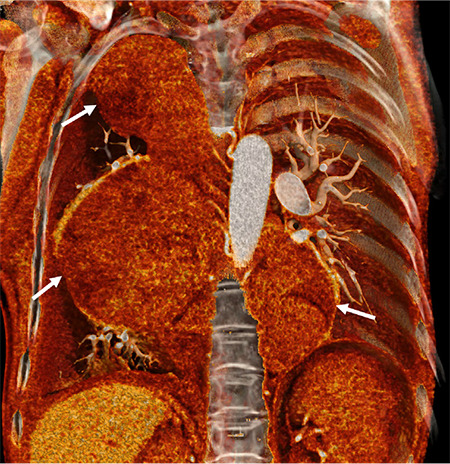

A Rare Cause of Giant Intrathoracic Mass in a Woman with Sickle Cell Disease: Extramedullary Hematopoiesis